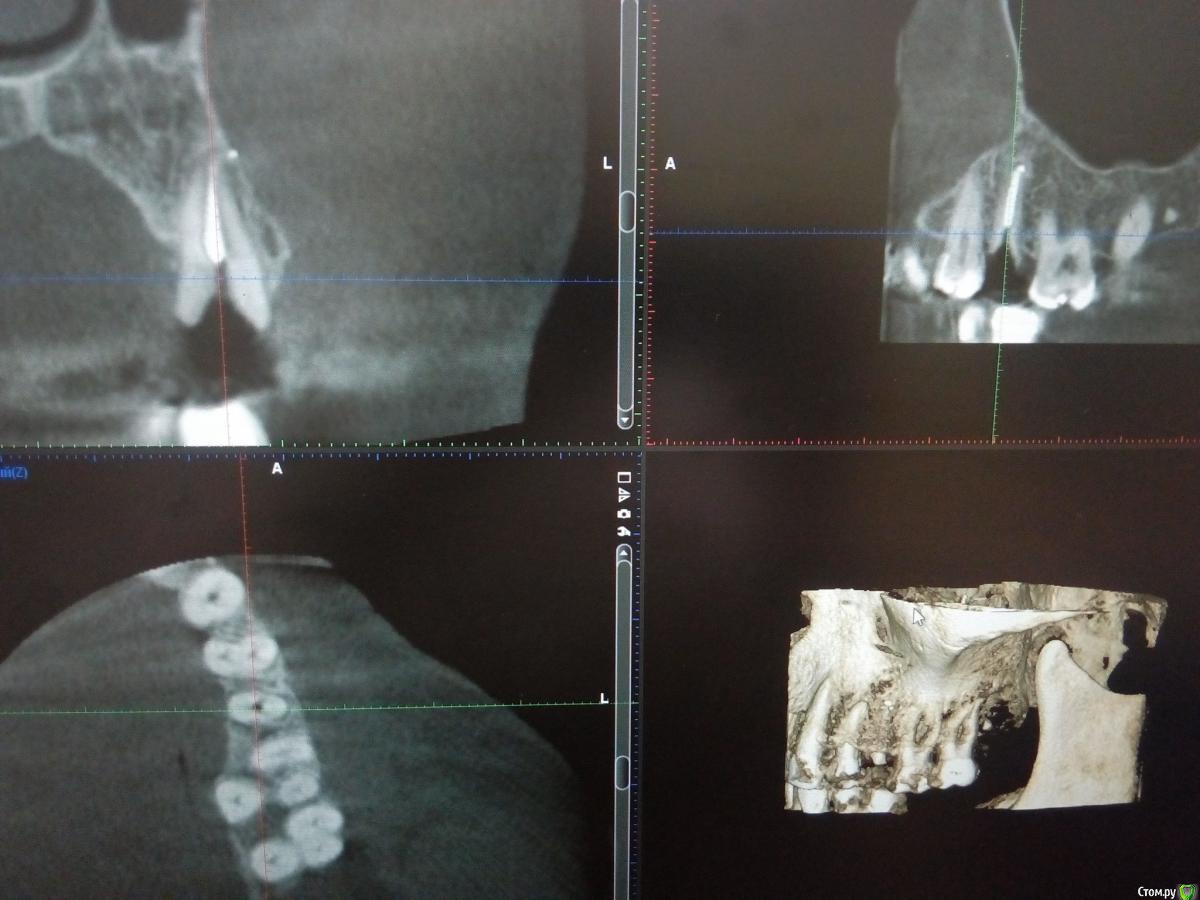

Sampson Опубликовано 10 августа, 2018 Поделиться Опубликовано 10 августа, 2018 (изменено) Очень мило для первого раза.. Здравствуйте коллеги.Сегодня поставил первый свой одномоментныйИзначальная картинаУдалениеСверление и контрольГрафтБолтКТФдмP.S. еще сдт взял с неба и вестибулярно подшил. А с неба заложил prf. Изменено 10 августа, 2018 пользователем Sampson 7 Ссылка на комментарий